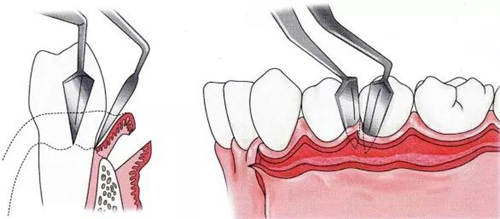

▼圖9  全厚瓣截面圖。手術(shù)刀到達骨面處后進行切開,為使骨面完全露出,使用骨膜剝離器,剝離含骨膜部分。

B半厚瓣(Partial thickness flap或Split thickness flap)翻瓣

▼圖11  半厚瓣斷層圖。通過將上皮和骨膜之間的結(jié)締組織切開,將骨膜殘留在牙槽骨上,形成不含骨膜的粘膜瓣。